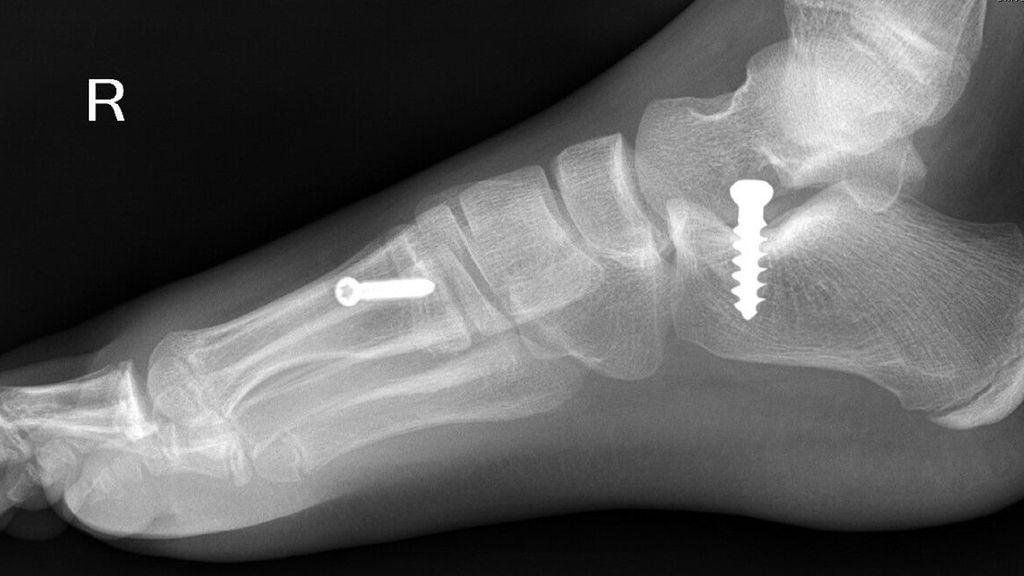

Verbleibende Valgusfehlstellungen im oberen Sprunggelenk über das 8. bis 10. Lebensjahr hinaus bedingen einen Knickfuß bzw. Rückfußvalgus, welcher in Kombination, aber auch ohne gleichzeitig vorhandenen Senkfuß bestehen kann. Dieser Rückfußvalgus lässt sich mit einer medialen Schraubenepiphyseodese am Innenknöchel gut korrigieren (Abb. 10), welche im Falle eines gleichzeitig vorhandenen abgeflachten Längsgewölbes mit einer Arthrorise (z.B. mit Calcaneus-Stopp-Schraube) kombiniert werden kann. Es wurde in zahlreichen Publikationen gezeigt, dass diese einen wachstumslenkenden Effekt auf die Plattfußdeformität hat, welcher auch nach Entfernung der Stopp-Schraube (routinemäßig nach etwa drei Jahren) verbleibt (Abb. 11).

Abb. 10 (links): MedialeSchraubenepiphyseodeseamInnenknöchel; 11 (Mitte): mit wachstumslenkendem Effekt auf die Plattfußdeformität, auch nach Entfernung der Stopp-Schraube; 12 (rechts):laterale Schraubenepiphyseodese des Os metatarsale I in Kombination mit einer perkutanen, medialen Bohrloch-Epiphyseodese der proximalen Phalange